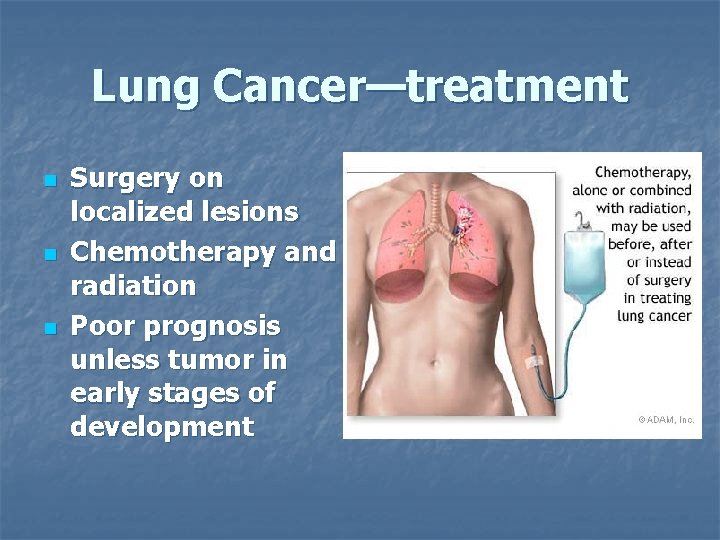

Lung Cancer—treatment n n n Surgery on localized lesions Chemotherapy and radiation Poor prognosis unless tumor in early stages of development